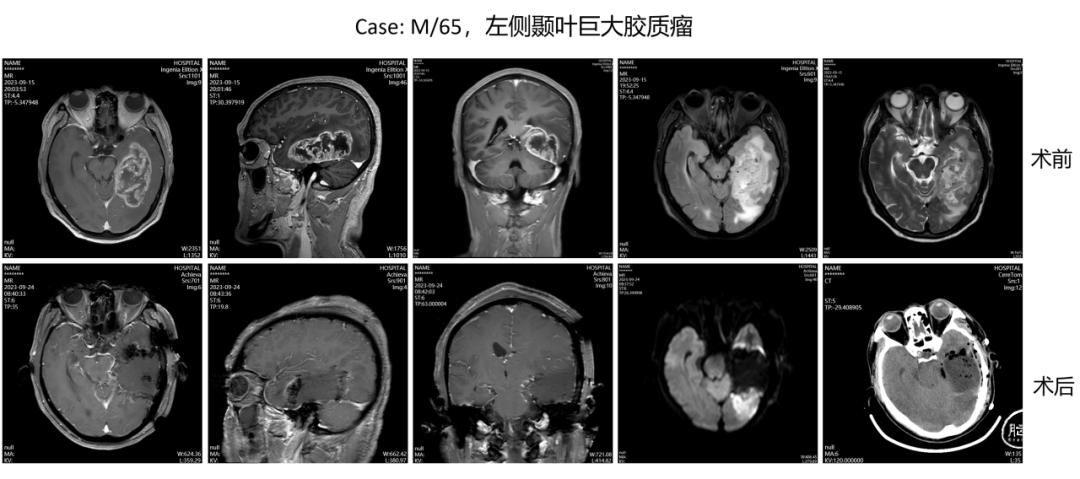

多模态影像评估和引导下脑内肿瘤的精准手术切除及机器人活检,此技术作为微侵袭神经外科的一种精准诠释,它结合了多模态影像评估、精准手术切除和机器人活检等多个方面,为脑内肿瘤的治疗提供了更为精准、安全和有效的手段,这项技术不仅提高了肿瘤的全切率,还降低了手术风险和并发症的发生率,改善了患者的生存质量。同时,机器人活检技术的引入也为脑内肿瘤的病理诊断提供了更为便捷和准确的手段。

胶质瘤是神经外科最常见的颅内原发性恶性肿瘤,其治疗手段包括手术、放疗、化疗、电场治疗等。手术是迄今治疗胶质瘤最有效的手段,但为了巩固手术效果,术后常需要结合放疗、化疗和电场治疗。故此,我院成立胶质瘤专病中心,此专病中心为国家级胶质瘤规范诊疗示范基地,其整合多学科力量,旨在为每位胶质瘤患者带来一种综合、个体化的治疗方案,提高患者的治疗效果和生活质量。